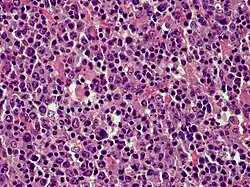

| Cutaneous diffuse large B-cell lymphoma | |

- Primary cutaneous diffuse large B-cell lymphoma, leg type

Because recent studies had shown that primary cutaneous marginal zone lymphoma, which was formerly classified as a subtype of the MALT lymphomas: a) has a distinct microscopic histology and gene expression profile; b) spreads to extracutaneous tissue in only 4 to 8.5% of cases; c) has a 5 year disease-specific survival in excess of 99% even in patients not receiving aggressive therapy; and d) has pathological findings that overlap the benign cutaneous disorders termed cutaneous lymphoid hyperplasia. Consequently, EORTC, 2022, renamed primary cutaneous marginal zone lymphoma as primary cutaneous marginal zone lymphoproliferative disorder.[3] Primary cutaneous follicle center lymphoma is also an indolent lymphoma.[4] The majority of patients achieve complete remissions following surgery and/or radiation therapy. Its spread to extracutaneous tissues is rare (10%) and has a 5-year overall survival and disease-specific survival of 87% and 95%, respectively.[3] Primary cutaneous diffuse large B-cell lymphoma, leg type is an aggressive B-cell lymphoma that is often resistant to therapy and carries a poor prognosis,[5] i.e., they have a 5-year disease-specific survival rate of 43% or 70% depending on whether their cancer cells have or do not have, respectively, inactivating mutations in both of their CDKN2A genes.[6]